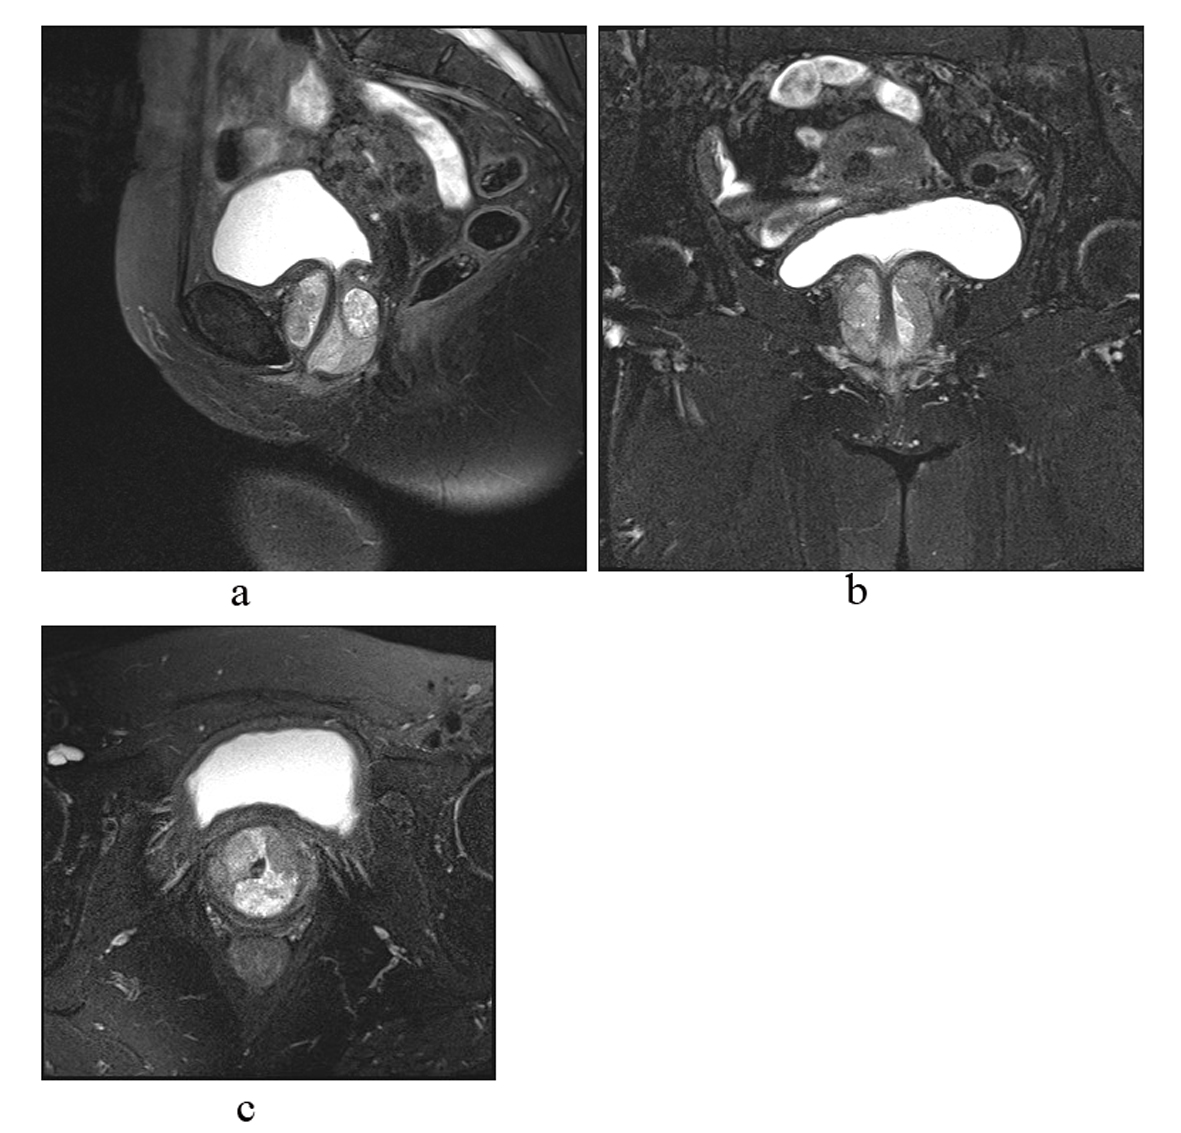

Magnetic resonance imaging (MRI) demonstrated a 3.7× 4.1 cm mass with solid and cystic areas wrapping around the urethra (Fig. 1). The prominent polypoidal solid areas in the anterior component of the mass were suggestive of a transitional cell malignancy. Urine cytology showed malignant cells consistent with urothelial carcinoma. Based on the images and cytology results the patient underwent urgent cystourethroscopy, this demonstrated a mass in the posterior wall diverticulum of the urethra. Multiple biopsies were obtained via a transurethral and transvaginal approach.

![]() Click for large image | Figure 1. MRI images of heterogenous mass within a urethral diverticulum. |